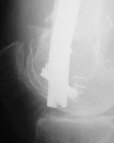

Attached are few examples from our Hospital:

Malpositioning is much too common (recurvatum, varus - valgus).

B. Fixation loosening: distal cutting of the nail, non-unions do happen (cases attached).

Locking Plating has more distal screws than any nail, fixed angles and provides much better fixation, especially in osteoporotic bone.